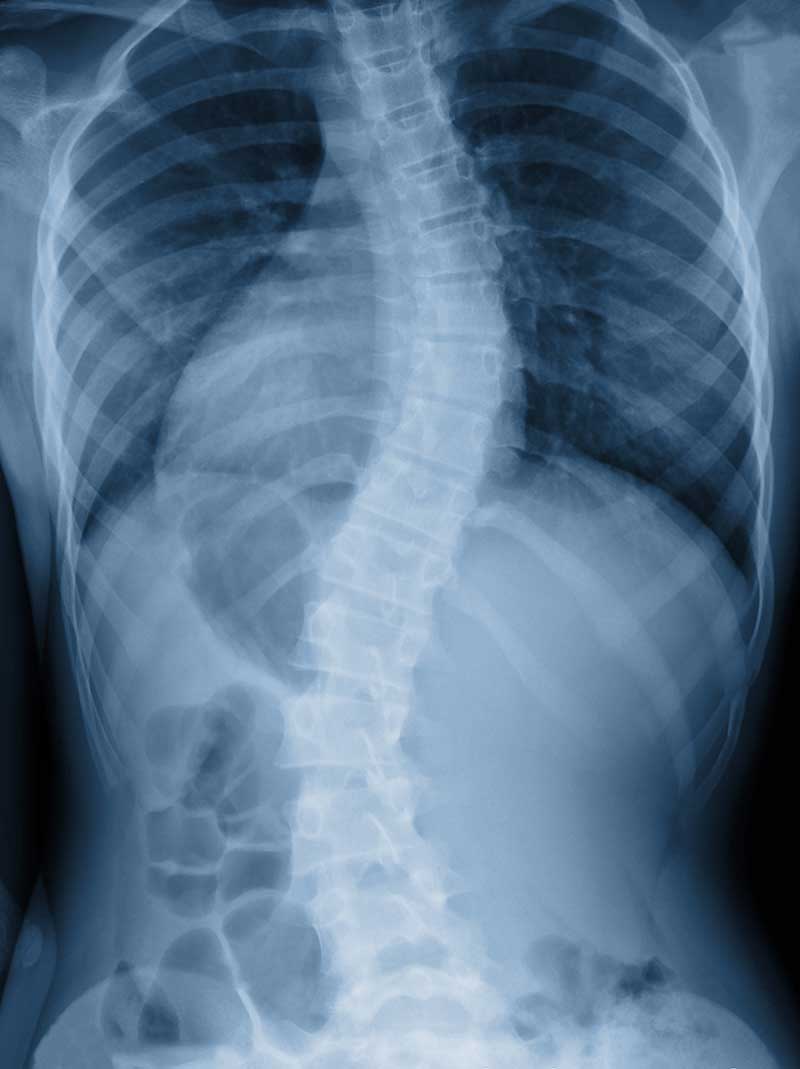

The specific cause of scoliosis has been studied for many of years but there is no evidence pointing to a specific reason. The studies do showcase that a young girl is more likely to experience scoliosis. Bends in the spine can originate from one single vertebrae being in the wrong position. As the individual grows, their body must compensate and alter to accommodate the misaligned vertebrae resulting in “S” and “C” shaped spines. Unleveled shoulders and pelvis are a common first sign to parents that their child may have the early signs of scoliosis. Scoliosis is not the same as other spinal issues as it can’t be fixed through an improvement in posture.

Scoliosis can be spotted from a consultation, but to understand the severity of the condition, an X-ray is needed. There are methods of detection that have been created to detect scoliosis without an X-ray. One of these techniques is known as the Adam’s Position test. This test consists of a series of bends allowing the practitioner to examine the shape of the spine. Here at Restorative Spine & Joint, we will check your shoulders and hips to ensure that they are level. In addition, we will ensure the legs are the same length as this is a common hint that scoliosis is beginning to develop.